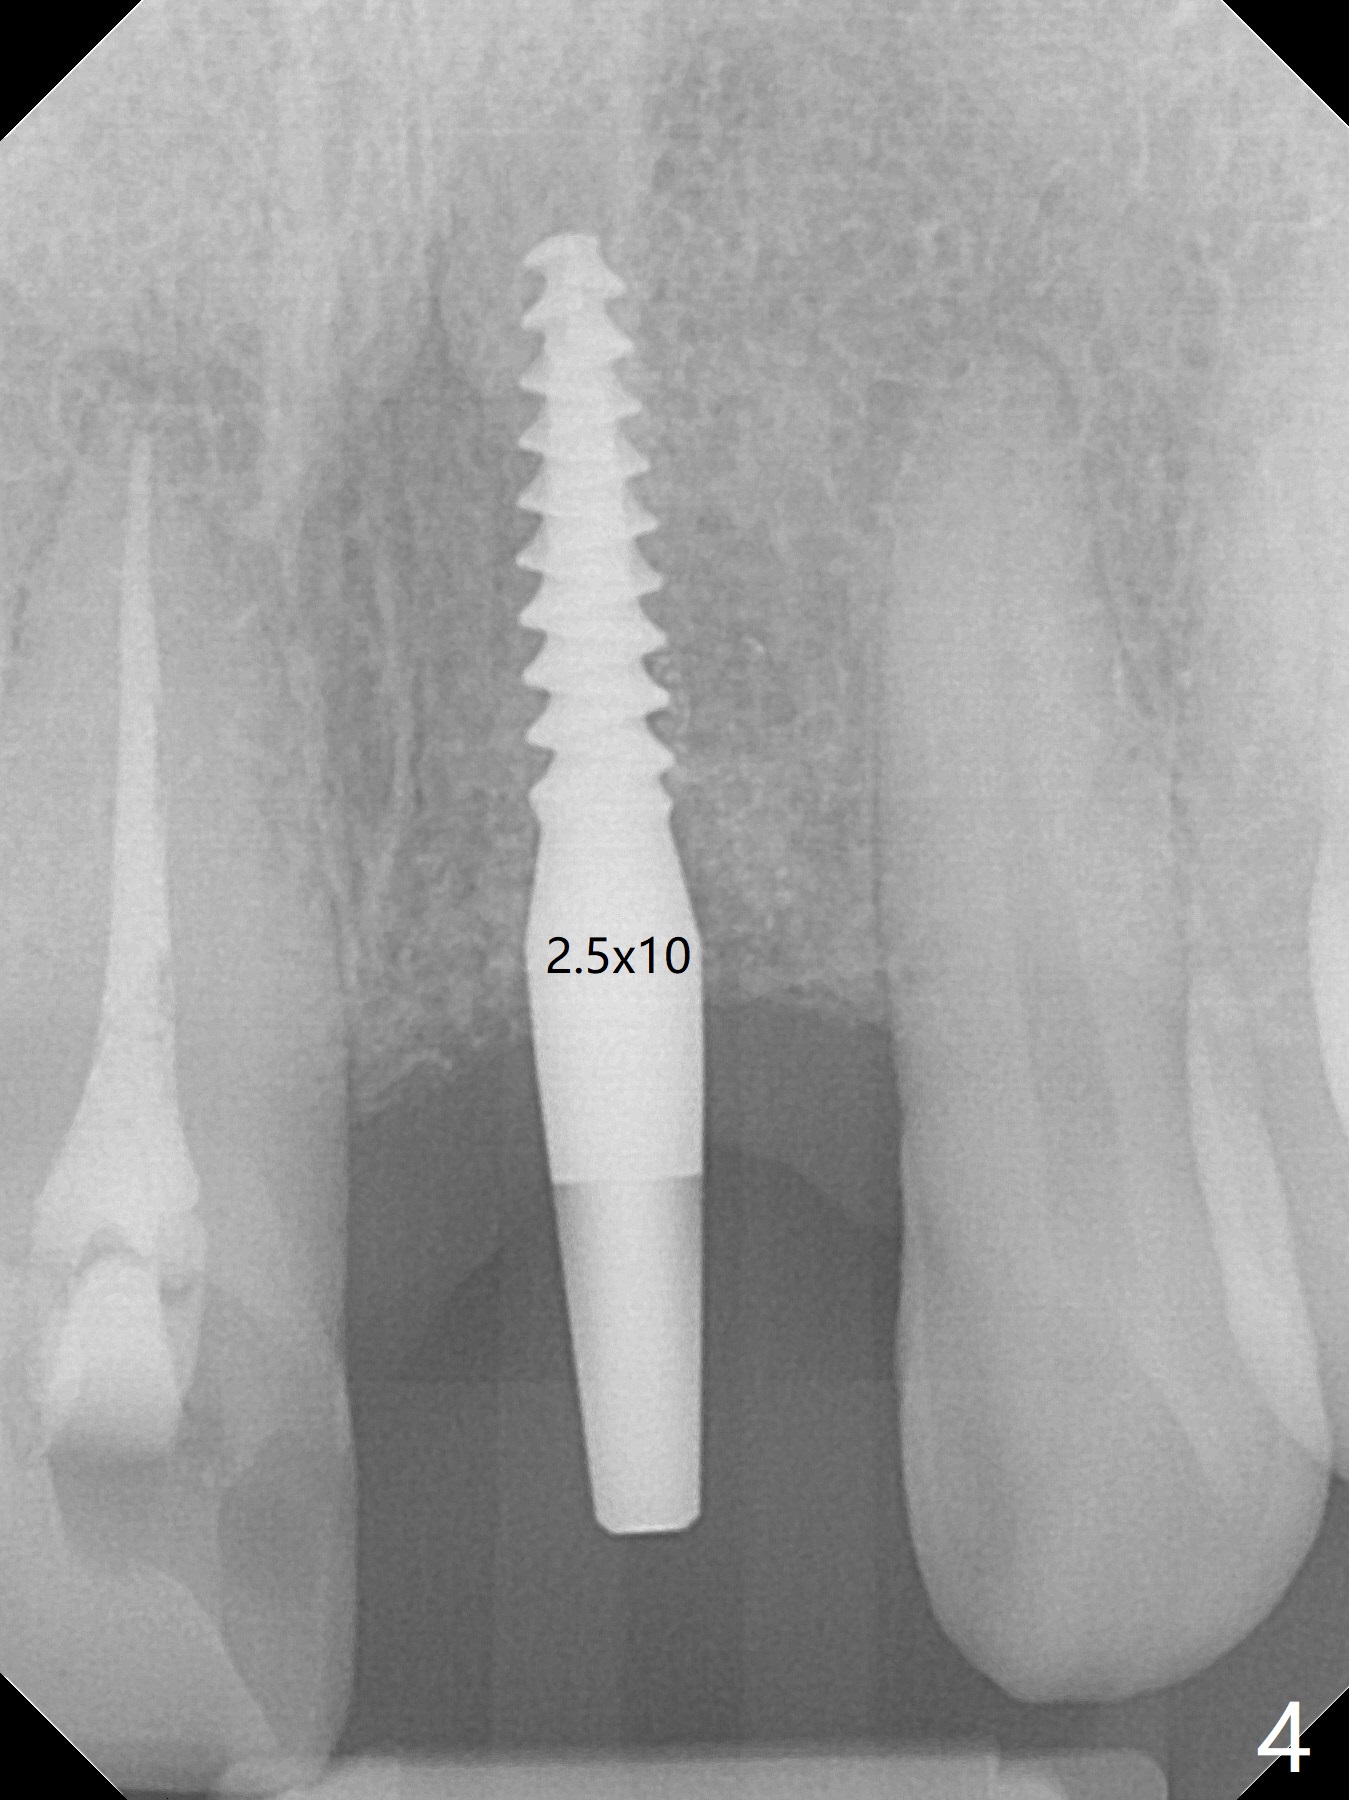

Except the depth, a 2.5x10 mm mini implant is placed with precision (in trajectory) at #9 (Fig.1-5). Confidence using surgical guide for the narrow ridge is enhanced due to placement of two digits against the buccal and palatal plates for tactile sensation. The depth issue is related to overprep with 2.2 mm drills. The torque is <15 Ncm. The immediate provisional is bonded to the neighboring teeth for retention. It appears that smaller drills should be made for guided surgery (such as 1.5 and 2.0 mm). The immediate provisional looks acceptable buccal and occlusal 3 weeks postop (Fig.6,7), although the palatal gingiva is erythematous (Fig.8, which is common after use of drill for access (tissue laceration), OHI offered). Three months postop (Fig.9), the palatal gingiva looks healthy (data not shown), while there is no bone loss around the implant (Fig.10). It remains the same 5 months postop (immediately post cementation, Fig.11) and 3,11 months post cementation (Fig.12,13). The labial gingiva is healthy (Fig.14), while the palatal one is less erythematous and edematous (Fig.15) than earlier (Fig.8).